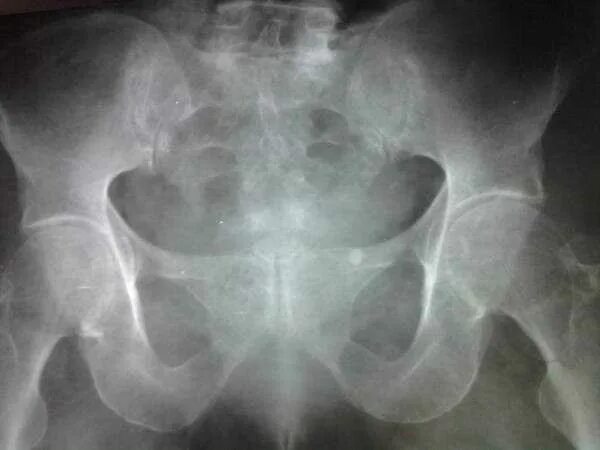

Симфизит при беременности 1 степень